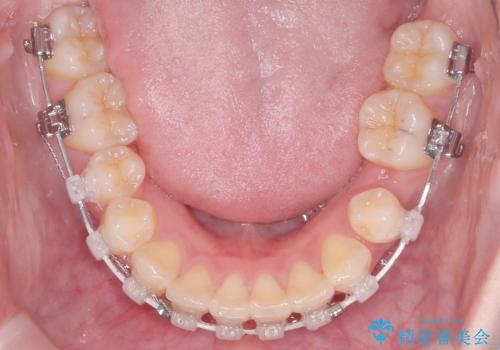

- 審美ワイヤー

精密検査の結果、歯を並べるスペースの不足に加え、上下の歯列の正中(中心)が大きくズレていることが確認されました。突出した口元を下げ、顎の左右バランスを整えるためのスペースを確保するため、右上・左上・左下の4番目(第一小臼歯)を計3本抜歯する計画を立案。装置は、治療中の見た目にも配慮し、目立ちにくい審美ワイヤーを選択しました。

治療は、抜歯によって得られたスペースを活用し、前歯を後方へ移動させながら上下の中心を一致させる緻密な調整を行いました。

特に下顎の右方偏位に対しては、ワイヤーによる繊細なコントロールを行い、左右の咬合バランスを整えることに重点を置きました。2年半の治療期間を経て、突出していた前歯は理想的な位置に収まり、顎のズレも大幅に改善されました。